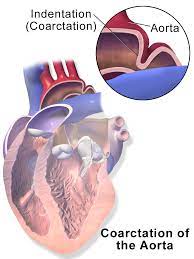

Overview

Package includes:

Days in hospital : 3 to 4 Days (For patient and one attendant)

Days in hotel : 8 Days (For patient and one attendant)

Room type in hospital : Shared

Room type in hotel : Private

Hotel category: Standard

Value added benefits of the Minimally Invasive Surgery with Carotid Endarterectomy:

Ø Doctor consultation charges

Ø Lab tests and diagnostic charges

Ø Room charges inside hospital during the procedure

Ø Surgeon Fee

Ø Nursing charges

Ø Hospital surgery suite charges

Ø Anesthesia charges

Ø Routine medicines and routine consumables (bandages, dressings etc.)

Ø Food and Beverages inside hospital stay for patient and one attendant.

Extra benefits:

ü Interpreter

ü Visa assistance

Ø Site tourism of the city

Ø Follow up with the doctor

Ø Airport pick up and drop

Ø Free online consultation with the doctor

Ø Priority appointments with the doctor

Ø Room upgrade from sharing to private